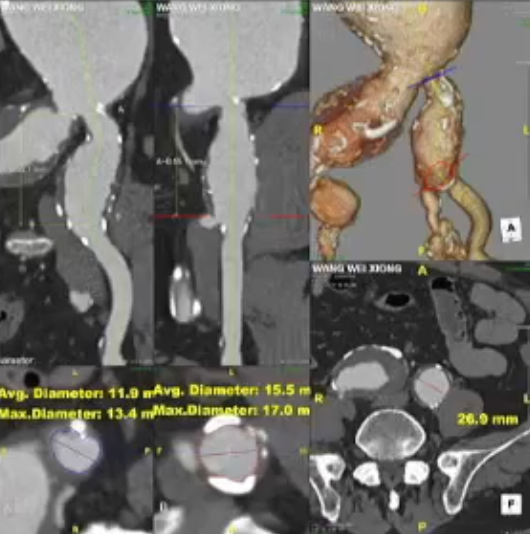

术前情况:74岁男性,肾下腹主动脉瘤,瘤体最大直径66mm,累及双侧髂总,右侧髂内扩张伴开口狭窄,左侧髂内夹层。

手术过程:根据患者及家属要求保双侧髂内,遂计划双侧髂内重建,右侧优先,左侧髂内情况尝试开通。手术中,先进行造影和翻山建立通路。

随后IBE主体就位,释放主体并翻山DSF鞘至短腿确认髂内情况,确认髂内健康锚定区情况及长度测量,释放髂内分支。对髂内支架狭窄处扩张,输送和释放第二枚髂内分支并手推造影确认通畅,IBE主体及各连接处后扩。

左侧髂内动脉超选与重建

右侧髂内动脉重建完成后,建立对侧翻山通路,再次确认主体位置及左侧髂内动脉情况。左侧髂内超选困难,经反复确认导丝配合导管超选真腔,手推造影确认髂内情况后释放远端VB,释放左侧髂内分支HGB并确认通畅情况。最后按常规EVAR置入腹主动脉支架主体,超选入主体短腿内对接IBE主体释放桥接喇叭腿。

术后情况:造影提示动脉瘤完全隔绝,手术成功实现了保留双侧髂内动脉并隔绝动脉瘤的目标,患者病情得到有效控制。